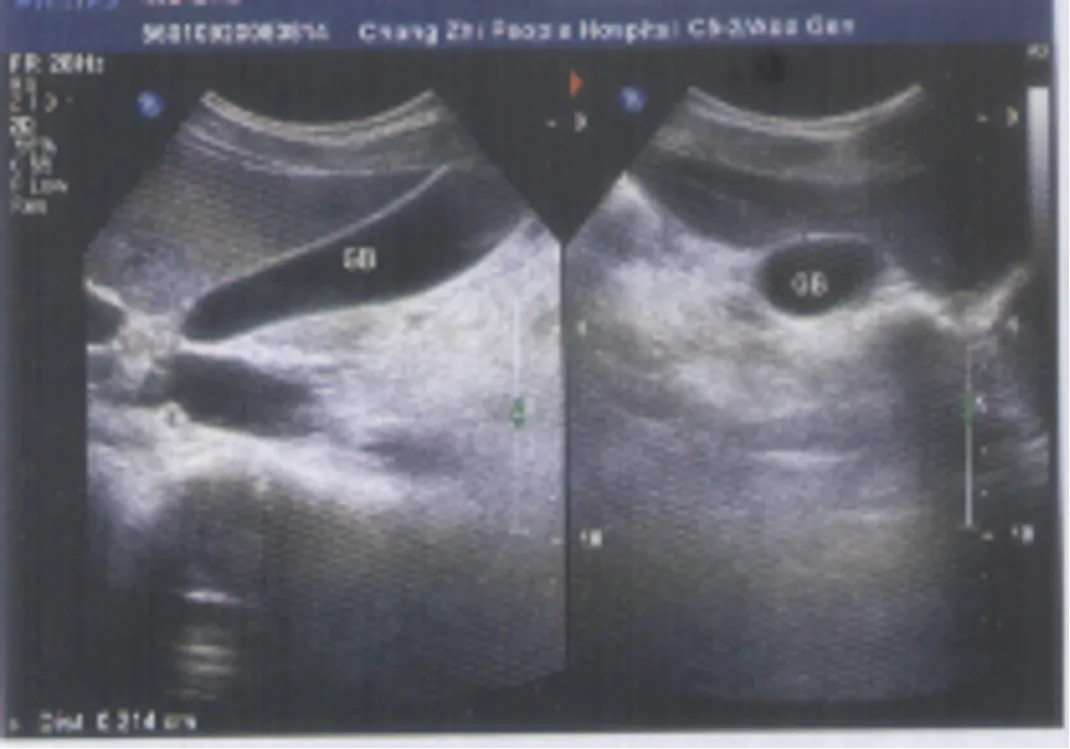

充填型胆囊结石

● 胆囊内胆汁较少或无胆汁,胆囊腔的无回声区消失,胆囊无正常的轮廓或形态,声像图仅表现为胆囊前壁呈弧形或半月状的强回声带,后方伴较宽声影,致使胆囊后壁不显示。

● 囊壁结石声影三联征(WES征:wall-echo-shadow征):前方为增厚胆囊壁的弱回声包绕中间结石的强回声,后方伴有声影。